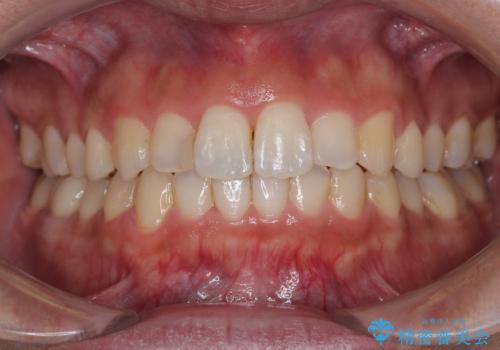

つぎはぎだらけの前歯をオールセラミッククラウンで自然な前歯に

膿の出口も認められたため、まずは根管治療を実施し、オールセラミッククラウンにて補綴治療を行うこととしました。

汚れがつきやすい状態のため、今後も継続してクリーニングを行っていく必要があります。